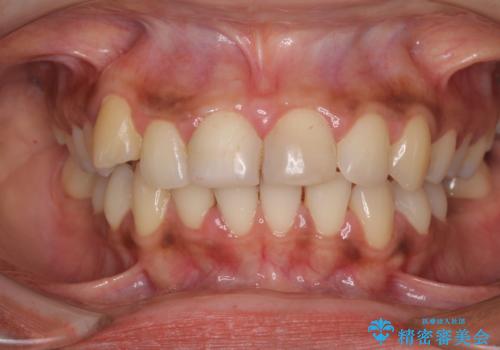

- 上の前歯2本の審美障害を気にして来院された患者様です。樹脂が無造作に充填されており、色合いも形態も不自然で、歯肉も腫れているため、オールセラミッククラウンにて補綴することとしました。

充填されたレジンを取り除いたところ、歯肉の炎症による出血が認められました。セラミッククラウン装着後は歯肉が腫れることもなく、仕上がりも自然な歯のようになり、患者様には大変満足していただきました。